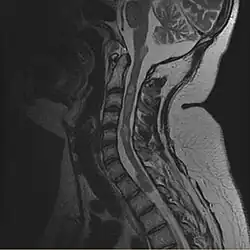

- Rückenmark: Ebenso häufig finden sich spinale (das Rückenmark betreffende) Raumforderungen (in der Medizin bezeichnet der Begriff Raumforderung in vielen Fällen eine Gewebswucherung). Bei den Patienten mit einer NF Typ II werden die cranialen (den Schädel betreffenden) Raumforderungen fast immer symptomatisch (z.Bsp. Hörminderung). Die spinalen Raumforderungen werden aber nur in ca. 40 % der Fälle symptomatisch. Die spinalen Tumoren werden in zwei Gruppen unterteilt. Einmal findet man intramedulläre Raumforderungen. Damit sind Tumoren gemeint, die sich in der Gewebssubstanz des Rückenmarkes finden. Hier findet man vor allem Astrozytome und Ependymome. Zum anderen finden sich extramedulläre Raumforderungen. Hiermit meint man Tumoren oder Gewebsveränderungen, die sich im Rückenmarkskanal, aber außerhalb der Rückenmarkssubstanz befinden. Der extramedulläre Raum ist der Spalt zwischen der Oberfläche der Rückenmarkssäule und der knöchernen Wand des Rückenmarkskanales innerhalb der Wirbelsäule. In diesen Fällen treten vornehmlich Schwannome und Meningeome auf.